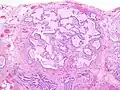

Appearance of usual interstitial pneumonia (UIP) in a surgical lung biopsy at low magnification. The tissue is stained with hematoxylin (purple dye) and eosin (pink dye) to make it visible. The pink areas in this picture represent lung fibrosis (collagen stains pink). Note the "patchwork" (quilt-like) pattern of the fibrosis. Appearance of honeycomb change in a surgical lung biopsy at low magnification. The dilated spaces seen here are filled with mucin. Hematoxylin-eosin stain, low magnification.

Appearance of honeycomb change in a surgical lung biopsy at low magnification. The dilated spaces seen here are filled with mucin. Hematoxylin-eosin stain, low magnification. A fibroblast focus in a surgical lung biopsy of UIP. Hematoxylin-eosin stain, high magnification. The white space to the left is an airspace. The pale area to the right is a fibroblast focus. It is an area of active fibroblast proliferation within the interstitium of the lung.